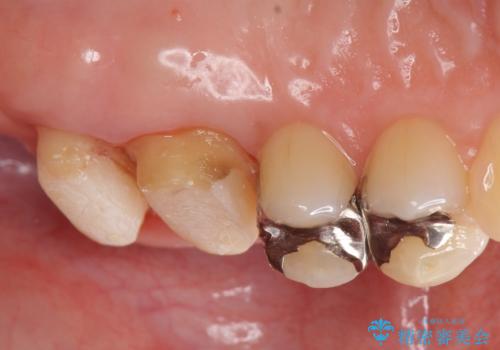

他院で入れた銀歯をやりかえたい。

- 銀歯をやりかえたいが他院で抜歯と言われセカンドオピニオンで来院。適合の悪い被せ物が入っており、まずは古い材料、虫歯をとり保存可能か確かめる必要があり、拡大鏡下で全て取り除いたら歯質が歯茎の中まで虫歯がありました。このまま無理やり型取りをして被せ物を作っても不適合な被せ物が入る可能性が高いため歯茎を切り取る手術(ディスタルウェッジ)を行いました。そして再根管治療を行いゴールドの被せ物で治療を行いました。